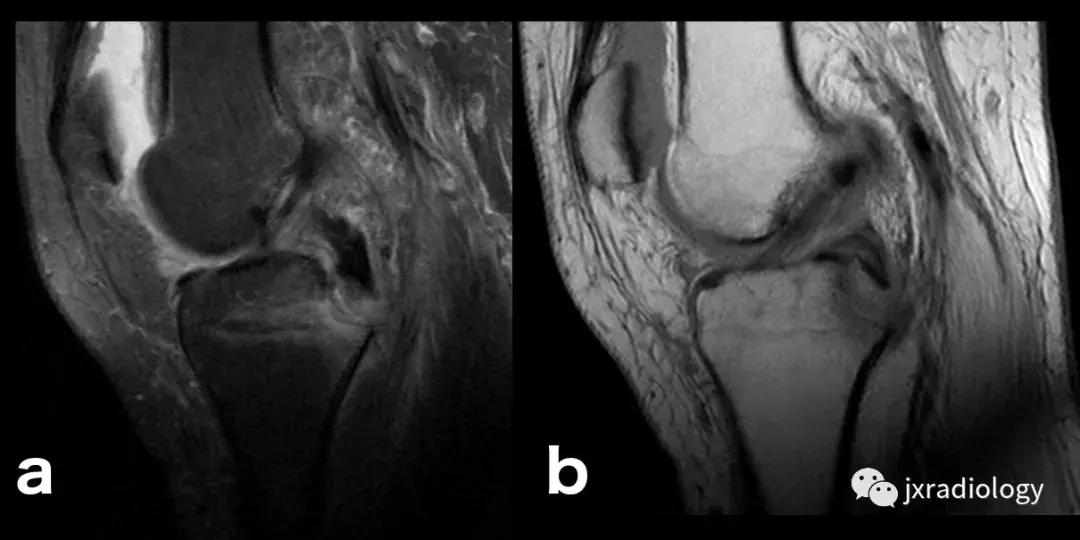

图8:创伤性骨髓水肿,髌骨脱位的典型病例:青年人,髌骨一过性脱位和挫伤的横断面(a,b,c),冠状面(d,e)和矢状面(f)的PD-FS-WI图像 :股骨外侧髁的前外侧和髌骨下内侧的故事水肿。对于进行运动的青少年或年轻人来说,在弯曲时需要膝盖扭转运动的情况更为常见。如该患者患有髌骨骨软骨损伤(*)和内侧髌股韧带(MPFL)撕裂(箭头)。